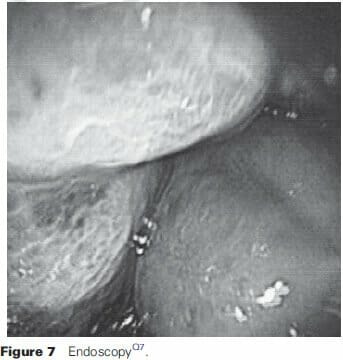

Endoscopy

Colonoscopy is crucial in the evaluation and workup of hemangiomas and malformations40,46. As noted with air-contrast barium enemas, the polypoid lesions can collapse with insufflation. The intraluminal characteristics have submucosal projections that range from blue to red (Figure 7). Pinpoint areas of bleeding are possible, with the presence of overt ulceration rarely seen. Mucosal edema, nodularity, and vascular congestion are present, and thus can be mistaken for the incorrect diagnosis of inflammatory bowel disease2,17,31. Hemorrhoids are also a frequent misdiagnosis.